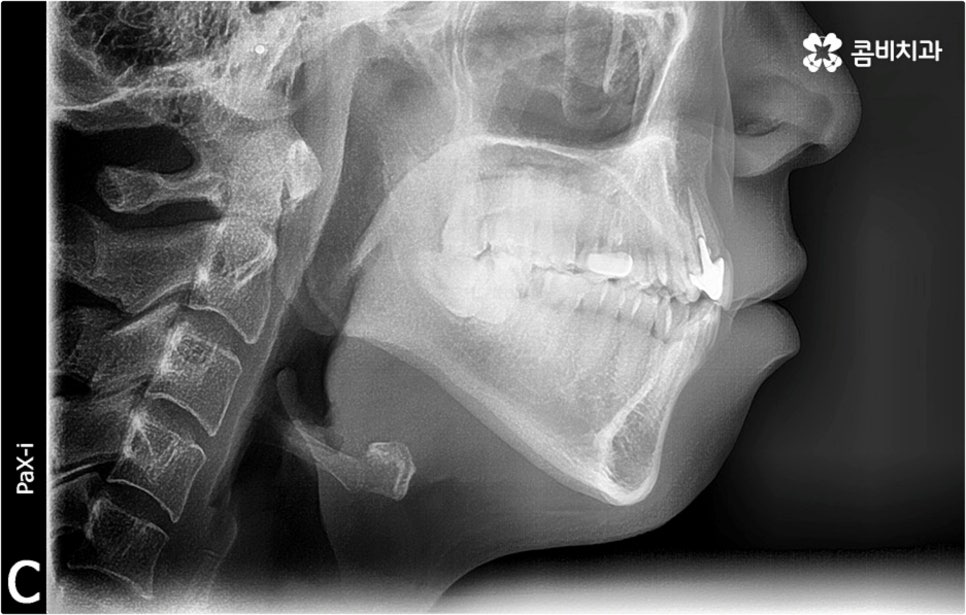

덧니 치료 방법은 어릴 때나 성인 이후나 크게 다르지 않으며 교정 치료 자체에 적기가 따로 정해져 있는 것은 아니지만 환자분들의 상황에 따라 잇몸뼈가 완전히 굳어지기 전인 성장기에 좀 더 빠르고 효율적인 결과를 얻을 수 있는 반면 중장년 이후에는 무리하게 치아를 이동시킬 경우 부작용이 발생할 수 있는데요. 이런 이유로 상대적으로 천천히 치아를 이동시켜야 해서 치료 기간이 길어질 수 있기 때문에 부정교합의 양상이 보인다면 10~12세 정도에 먼저 숙련된 치과교정과 전문의 선생님께 정밀 진단을 받아보시고 언제가 좋을지 치료 시기를 신중하게 조율해 보시길 권유드리고 있어요.

오히려 경우에 따라 무리하게 발치를 할 경우 혹시 모를 부작용, 즉 너무 많은 치아 이동으로 인해 입이 들어가 보이는 합죽이 같은 결과로 이어질 수 있어 주의하실 필요가 있어요. 특히 환자분들 각자에게 맞는 치료 계획을 세울 때 구강 구조, 교합, 상하악 골격 등 기능적인 부분과 함께 연령별 특성에 따른 골밀도나 발달 상황 등을 전체적으로 고려하지 않고 일부만 선택적으로 개선하려고 하면 추후 턱관절과 저작력에 계속 문제가 생길 수 있으며 잇몸 상태를 고려하지 않은 채 무리한 진행을 하게 되면 치아와 잇몸 건강에 좋지 않은 영향을 줄 수 있기 때문에 교정 치료는 의료진의 섬세한 기술력을 요하는 복잡한 고난도 진료라고 할 수 있습니다. 임상 경험이 풍부하고 다양한 케이스에 대한 노하우를 가지고 있는 숙련된 담당의 선생님과 함께 하는 것이 굉장히 중요한 포인트인 거예요.

정밀 검진 후 상담을 통해 덧니교정 치료 계획을 자세하게 듣고 중간 중간 진행 과정에 대한 브리핑을 받는 등 담당의 선생님과 지속적으로 소통하게 된다면 1~2년 정도 비교적 오래 걸리는 기간 동안 보다 편안한 마음으로 치료에 임하실 수 있으실 거예요. 이를 위해 3D CT 같은 정밀 진단 장비를 갖추고 있는지, 처음부터 끝까지 의료진의 변화없이 책임 진료하는지 꼼꼼히 따져보고 치과를 선택하는 게 필요하다고 할 수 있어요.